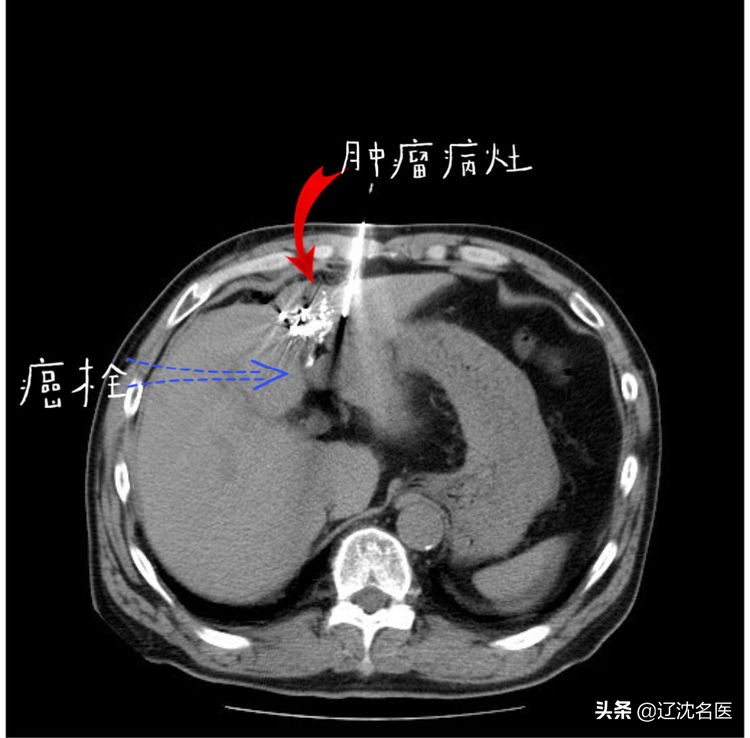

粒子植入术中定位

粒子植入手术术中穿刺